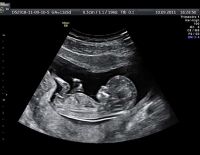

Việc siêu âm thai 10 tuần và những lưu ý dành cho mẹ

Siêu âm thai 10 tuần là việc làm cần thiết đối với sự phát triển của thai nhi cũng như tình hình sức khỏe của mẹ. Sau khi khám xong mẹ sẽ biết mình nên chăm sóc cơ thể như thế nào, có cần điều...